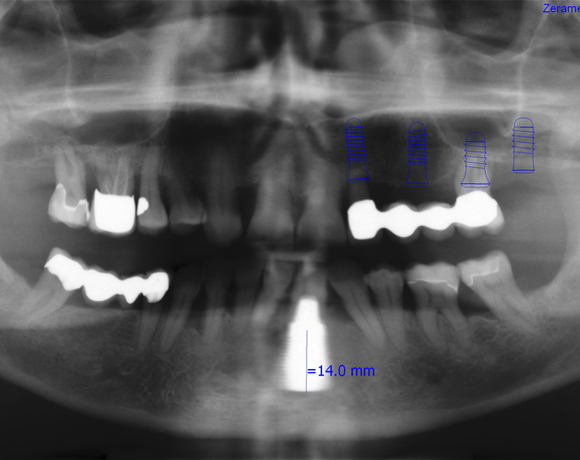

Zeramex P Implantate für die Zähne 22-27

Ein Projekt aus dem Jahr 2013

Bei dieser Patientin mussten die Zähne 22,26 und 27 aus parodontalen Gründen entfernt werden. Nach Extraktion der Zähne 22 und 26 wurden sofort in die Extraktionsalveolen die Implantate gesetzt. Zahn 27 war bereits sechs Monate zuvor extrahiert worden und die Knochenwunde gut ausgeheilt. Das geringe Knochenangebot wurde mit einem internen Sinuslift ausgeglichen. Im Bereich des Zahnes 23 wurde noch ein weiteres Implantat gesetzt. Da der Zahn 12 nicht angelegt und die Symetrie auf dieser Seite gestört war, wurden die Zähne 11 und 13 mit Teilkronen versorgt, um die Lücken zu schließen der Zahn 13 zu 12 umgebaut.